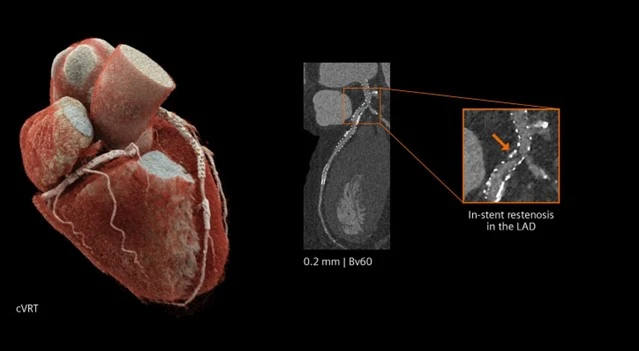

- Độ phân giải không gian rất cao: Do không sử dụng scintillator và vách ngăn quang học, pixel vật lý của đầu dò PCCT nhỏ hơn đáng kể so với EID, cho phép đạt độ phân giải không gian hiệu dụng lên tới 0.2 mm trong các chế độ chụp độ phân giải cao. Điều này góp phần làm giảm hiệu ứng thể tích từng phần, qua đó cho phép quan sát rõ ràng các cấu trúc kích thước nhỏ như mạch máu ngoại vi, tiểu phế quản, bè xương và chuỗi xương con tai giữa…

Tim mạch

- CT mạch vành: giảm nhiễu do vôi hóa và kim loại, giúp đánh giá lòng mạch chính xác hơn.

(Courtesy of Diagnostikum Graz, Austria)